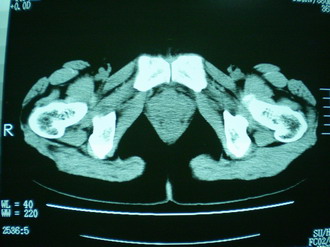

子宫增大,内可见类三角形低密度区,子宫后方可见类圆形团块状影,内部密度不均匀,可见靶样结构,结合病史考虑1子宫后方宫外孕(宫内假孕囊形成)2子宫肌瘤合并妊娠

子宫明显前倾,增大,宫颈增大呈分叶状。子宫直肠窝见不规则形水样低密度。(膀胱胀尿不理想)

考虑:1、宫颈部占位;

2、子宫直肠窝少量积液(盆腔炎所致)。

考虑:1、宫颈部占位(宫颈癌?);

2、子宫直肠窝少量积液。

1、前曲子宫,2、宫颈部占位?3、盆腔及右输卵管积液?宫内积血?4、左侧卵巢囊肿。